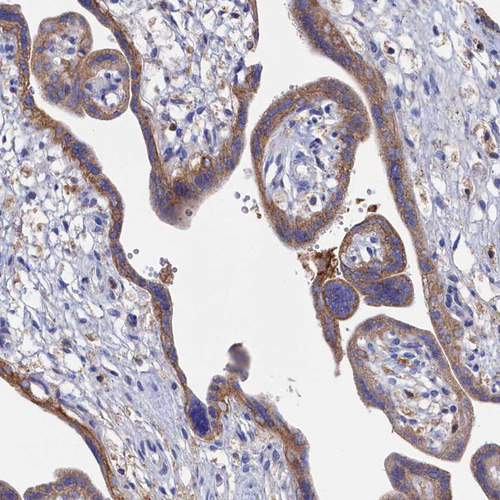

Immunohistochemical staining of human cerebral cortex shows strong positivity in neuropil.